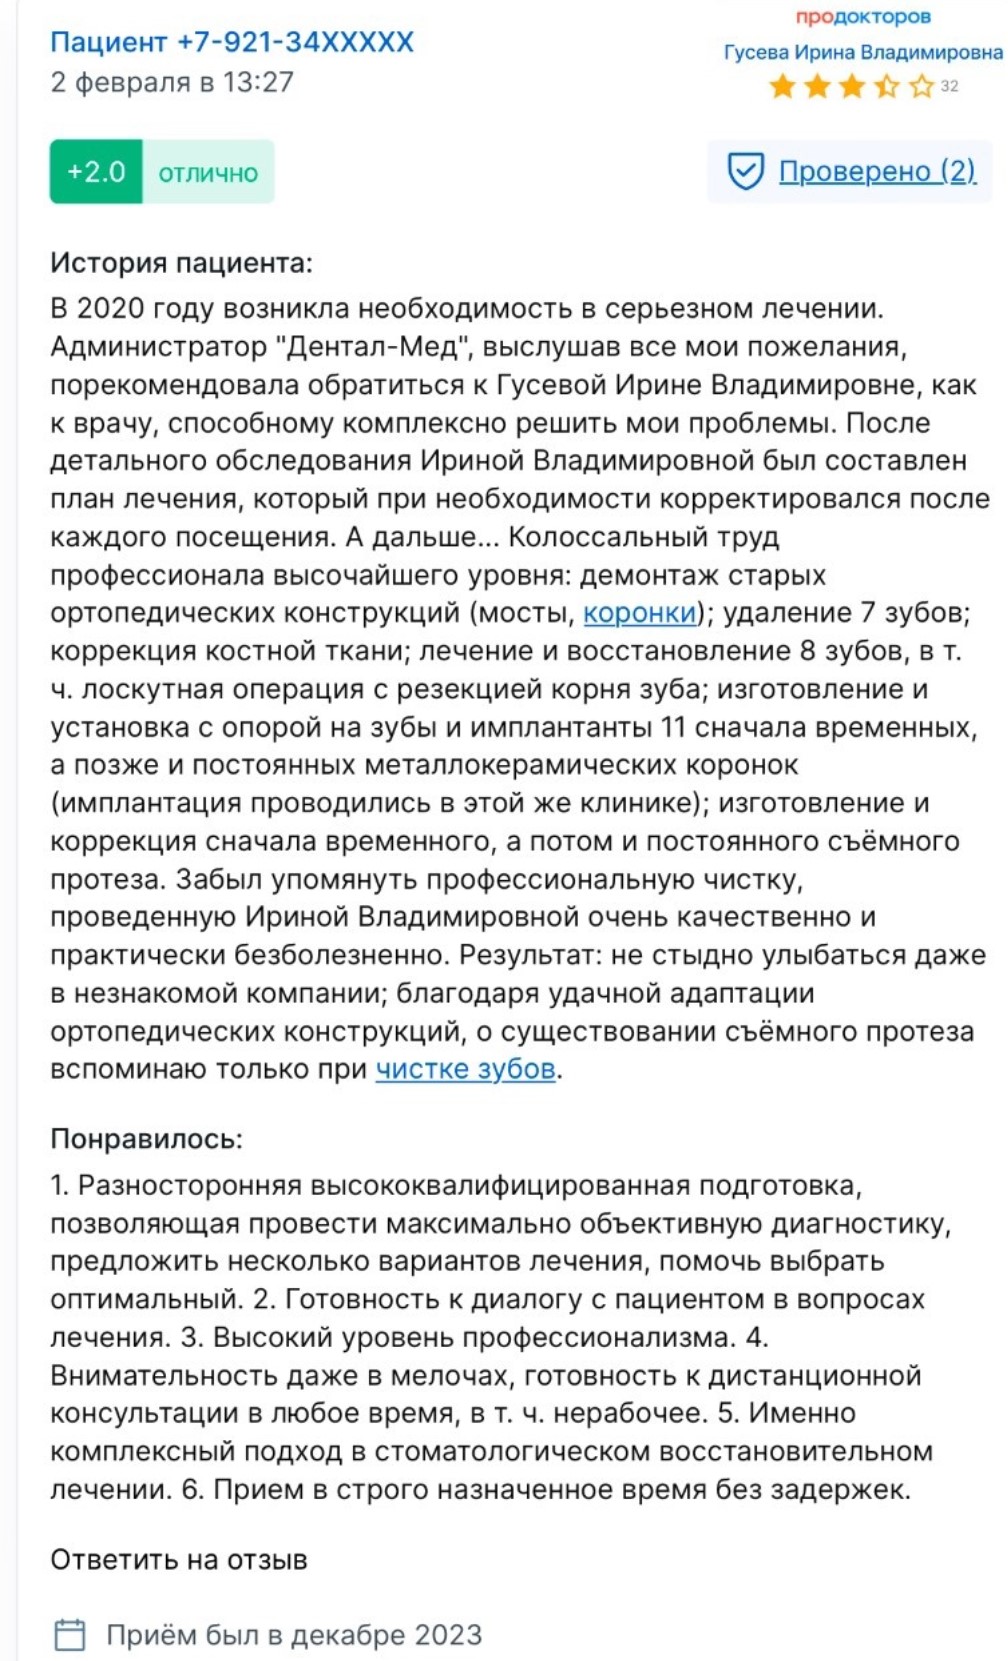

Ирина Гусевастоматолог-терапевт, имплантолог, ортопед

Ирина Гусевастоматолог-терапевт, имплантолог, ортопед